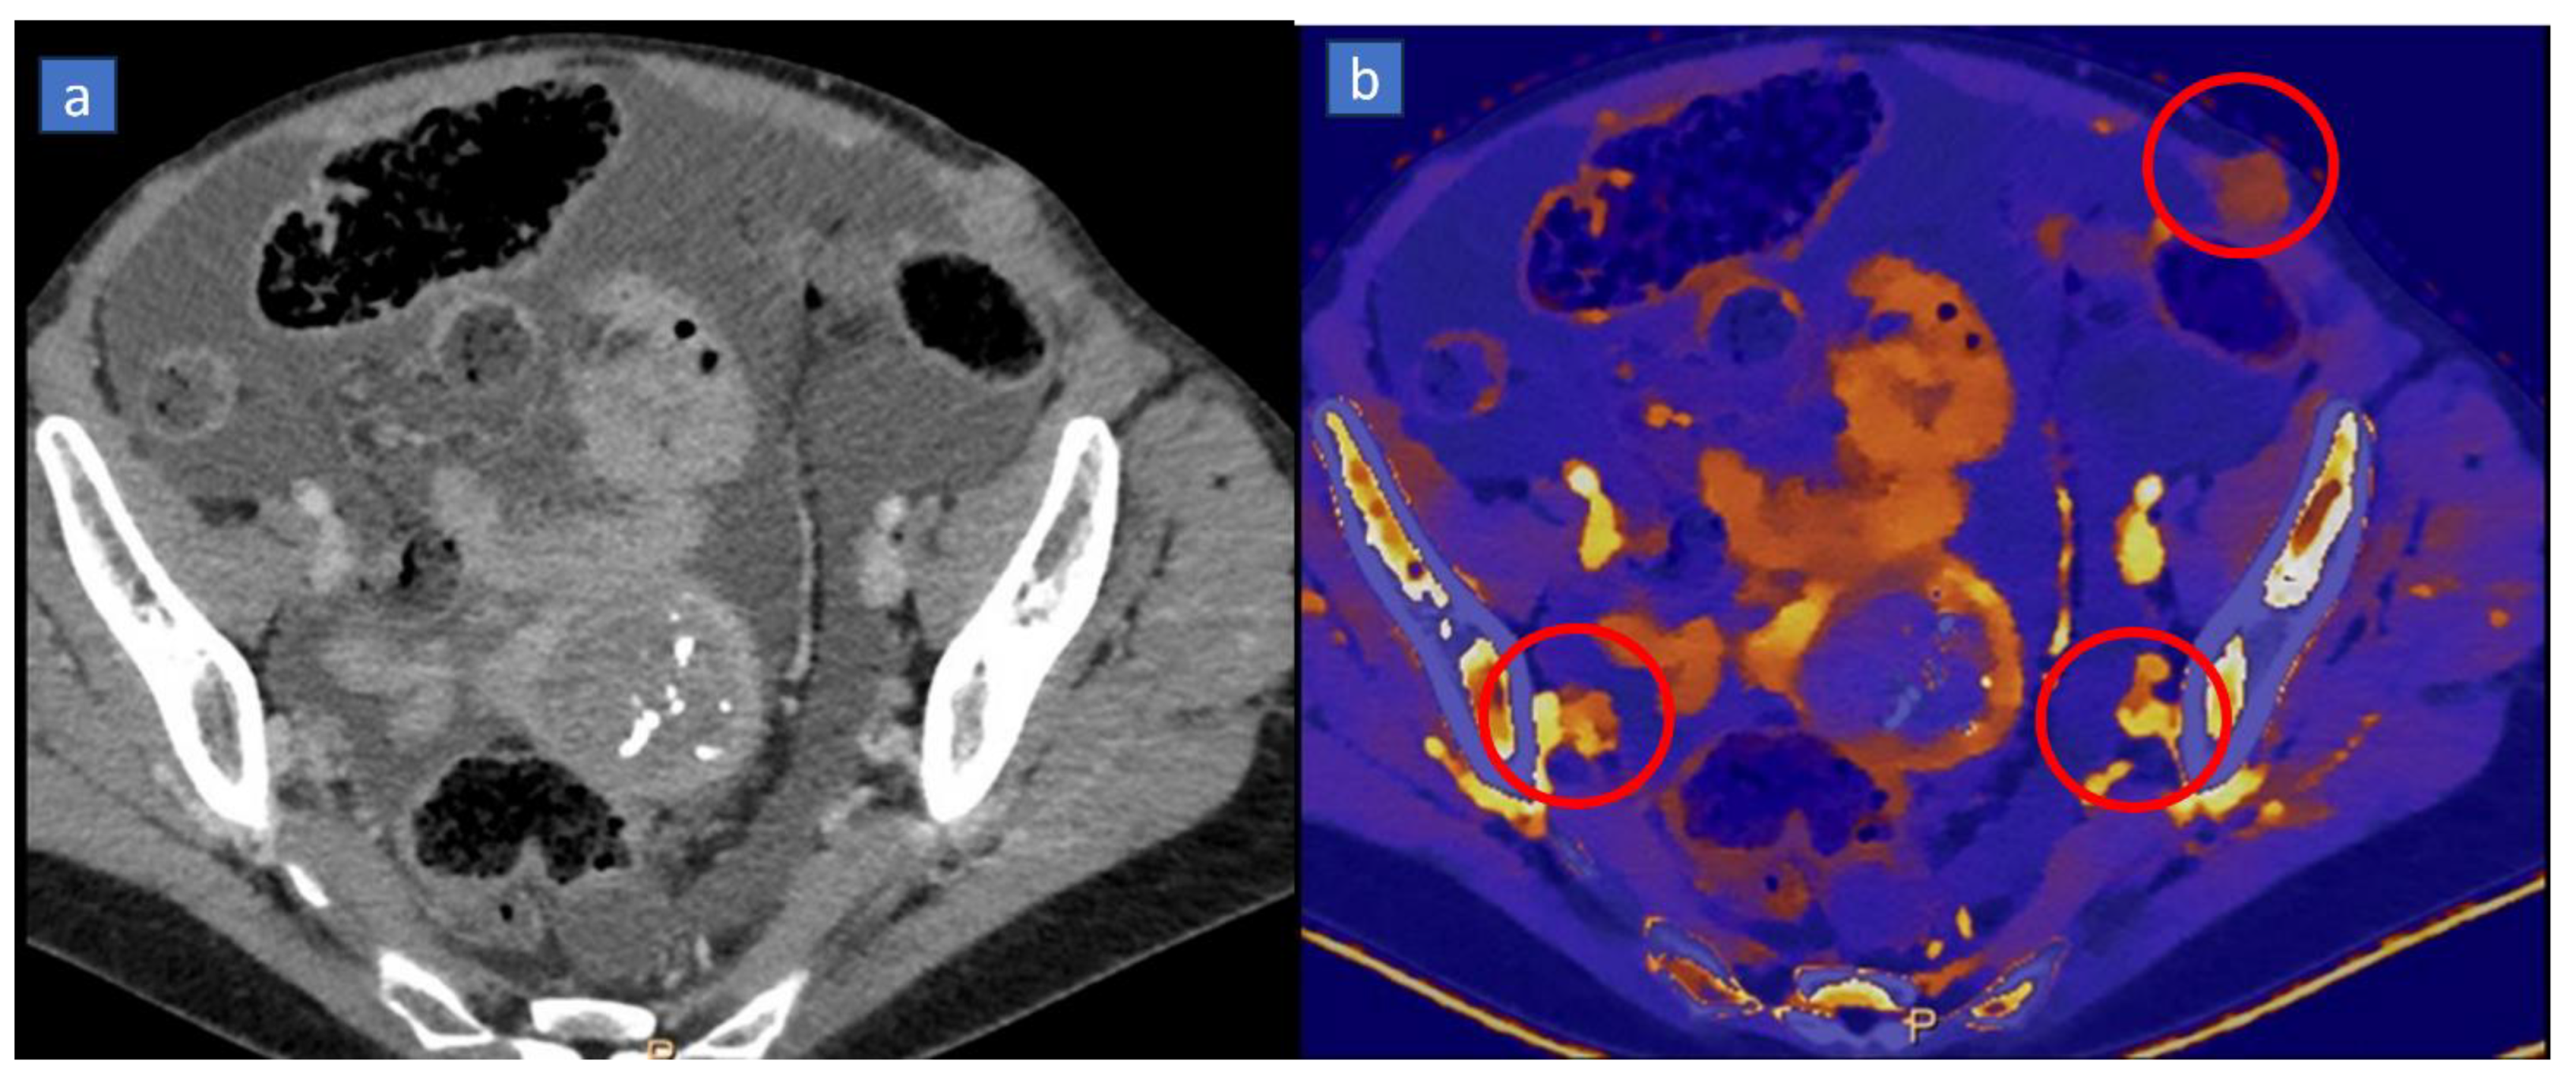

3. Iodine MAP

3.1. Applications